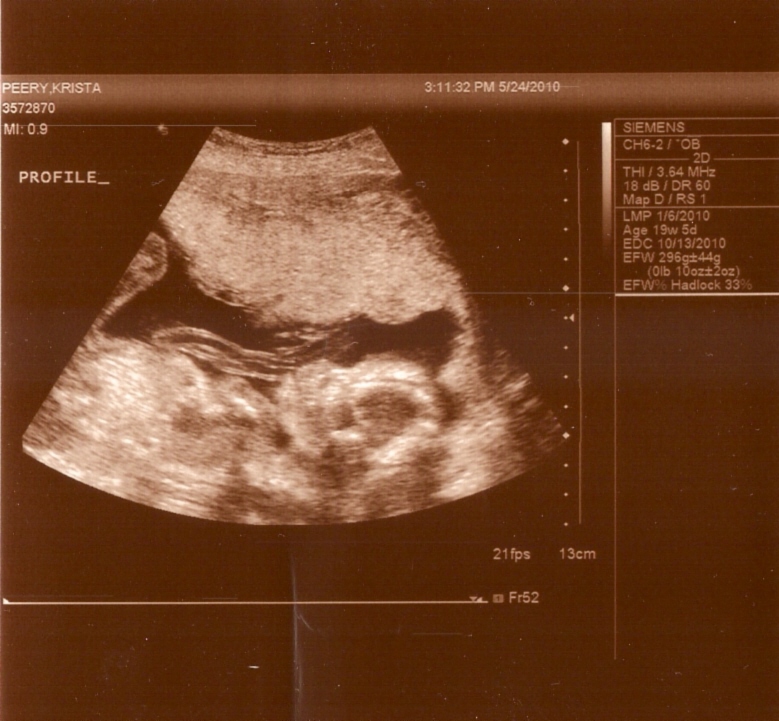

Her cute little profile